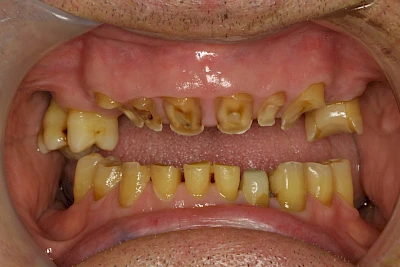

- Abnutzung durch Kauen (Abrasion) oder duch durch übermäßiges Knirschen bzw. Pressen (Attrition)

Auswaschung (Erosion) dagegen ist eine Verschleißerscheinung der Zähne aufgrund von immer wiederkehrenden Säureangriffen durch die Nahrung, verstärkt zum Beispiel durch den Genuss säurehaltiger Getränke oder Speisen. Auch bei Menschen mit einer Essstörung (z. B. Bulimie) können die Zähne durch die Magensäure ausgewaschen erscheinen.

Eine Sonderform sind sogenannte keilförmige Defekte im Bereich der Zahnhälse. Hier geht man davon aus, dass Knirschen und Pressen in Kombination mit falschen Putzgewohnheiten (zu hoher Putzdruck, Verwendung von Zahnpasta mit hohen Abrasionswerten) eine Rolle spielen.